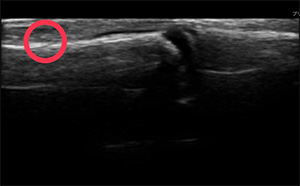

実例②

30代のお母さんが、子供と遊んでいて公園で転倒しケガをする。

手首の骨にキズの疑いがある為、提携先の整形外科に紹介しました。